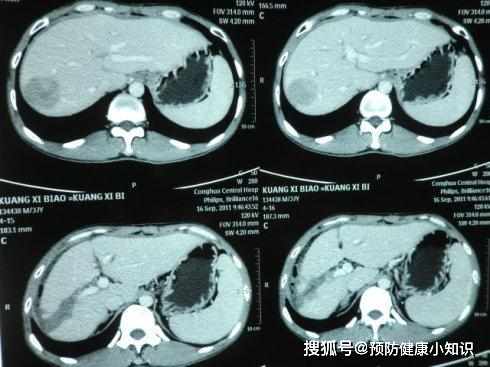

甲胎蛋白竟高達490,進一步檢查後,發現肝臟內有一個腫瘤,確診肝癌!已經到了中晚期了。

一般來說,出現右腹部疼痛的時候,可能病情已經發展到中晚期了。

肝臟病變的原因若是因為肝內出現腫瘤,那麼不及時醫治就會出現右腹部疼痛的感覺。

因為腫瘤會不斷長大,肝臟外面具有一層"薄薄的衣服",也就是肝臟包膜。

腫瘤不斷長大,會牽扯包膜,產生疼痛感。